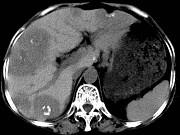

问题 女,55岁,腹胀,肛门闭气,消瘦乏力,肝区疼痛,CT检查如图,最可能的诊断为()

选项 A.多发性肝脓肿 B.肝癌肝内转移 C.肝淋巴管瘤 D.肝脏囊腺瘤 E.结肠癌肝转移

答案 E